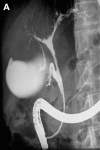

Patients: All nine patients had previously required long term treatment in an intensive care unit for septic shock: two patients with polytrauma, five with burn injury, and two with extensive surgery. They were admitted to our hospital because of cholangitis. Endoscopic retrograde cholangiography revealed severe intrahepatic stenoses in all patients and liver biopsies showed typical signs of sclerosing cholangitis. No patient had pre-existing liver disease.

Results: Mean follow up time was 35 months. In patients with major bile duct stenoses (3/9), 12 endoscopic dilations were performed in total. In one patient, concrements were extracted and intermittent stenting was necessary. To date, 4/9 patients have rapidly developed liver cirrhosis. During follow up, 5/9 patients died: two after fulminant cholangitis, one after liver failure, one due to liver transplantation associated problems, and one after cerebral ischaemia. One patient has been registered for transplantation and the remaining three patients show no acute signs of liver failure.